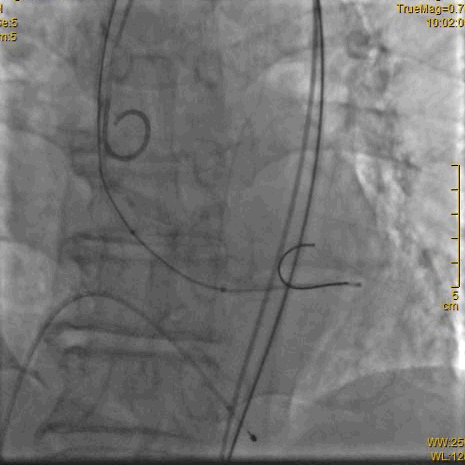

瓣膜释放过程

瓣膜完全释放后造影,形态良好,无周漏

主动脉重度狭窄行经股动脉的TAVR手术是外科手术禁忌或高危患者的一种手术治疗选择,在多学科协作下,广西国际壮医医院心病科徐先增教授团队完成VitaFlow Liberty™主动脉瓣置换。两个小时紧张有序的操作,术中在第一次瓣膜定位释放移位后,借助VitaFlow Liberty™的电动可回收技术,瓣膜第二次精准定位植入,术后造影检查和心脏彩超评估瓣膜形态活动良好,零压差,无瓣周漏。手术取得圆满成功,患者心功能改善显著。